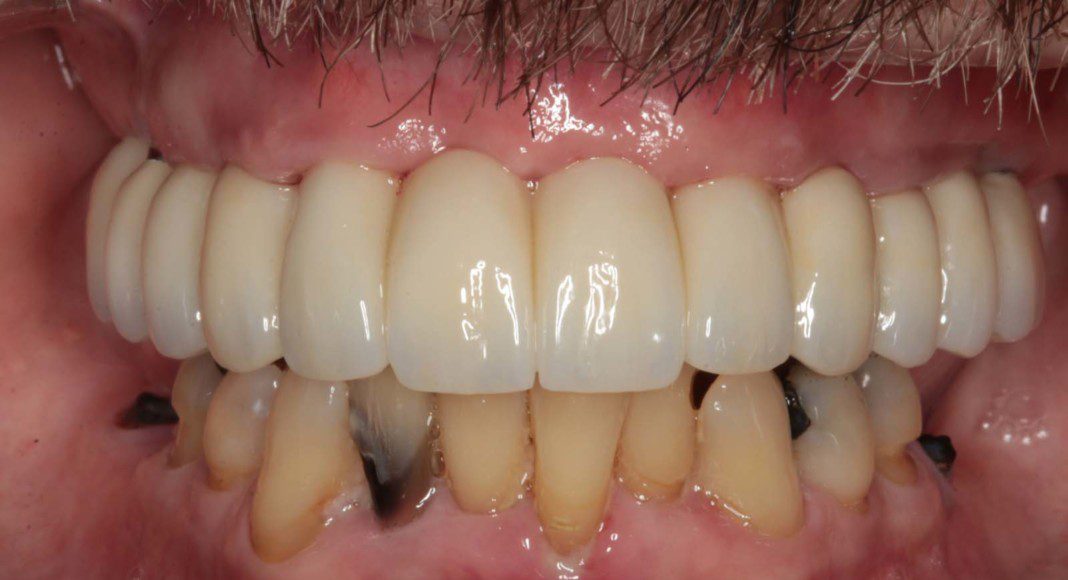

Mirror view of the tissues before delivery of the zirconia, implant bridge. Note the excellent volume of good, pink tissue (keratinized tissue). This good tissue is what allow the bone to remain healthy and full for many years if not forever.

Right lateral (mirror) view of bridge. Note the “normal” contours that mimic natural teeth. Slight metal exposure of implant #4. Nothing can be “perfect” and we try to keep this from happening. However, some patients have existing bone loss that prevents perfection.